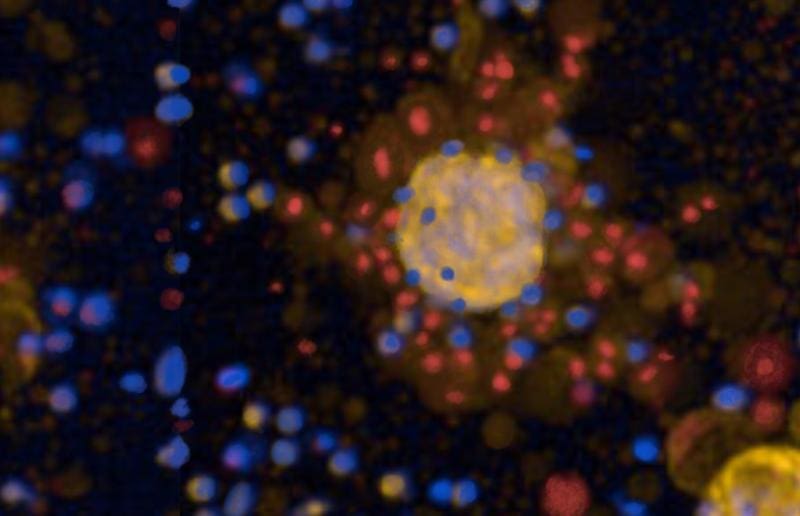

Lung cancer occurs in a highly individual form, with different characteristics that influence the success of therapy. Without knowledge of these characteristics, effective treatment is difficult. Existing options such as surgery, radiation, chemotherapy and immunotherapies often fail. The new method grows tumoroids from surgically removed tumor samples from patients at Charité. These mini-tumors allow tests of different approaches in the laboratory.

First, the researchers validated the tumoroids using classic chemotherapies. They then tested the efficacy of CAR-T cells, an immunotherapy in which T cells are genetically modified to specifically recognize and destroy cancer cells. CAR-T cells have proven effective in blood cancers, but development remains challenging in solid tumors such as lung cancer. The tests showed that it is not only the frequency of target molecules on tumor cells that determines whether CAR-T cells are successful. Tumor’s own protective mechanisms and immune escape strategies play a decisive role. Healthy lung organoids served as a control for possible side effects.